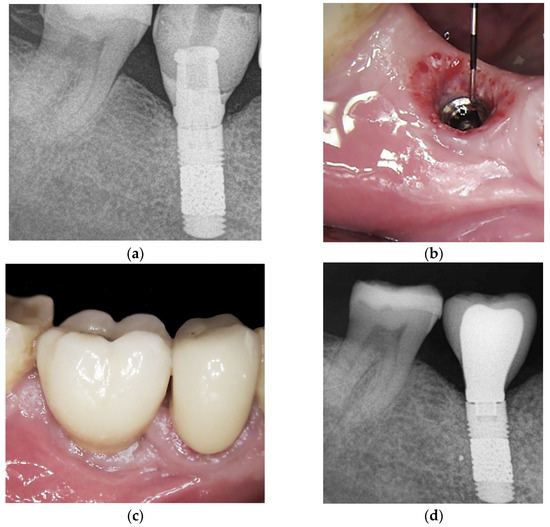

2.4. Surgical Protocol

- Bone level changes were evaluated by comparing the measurements at baseline (on the day of prosthesis delivery) with those at follow-up visits. Measurements were obtained with an intraoral radiograph that depicted the vertical distance between the implant shoulder and the most coronal bone contact with the implant surface at mesial and distal sites. All the intraoral radiographs were taken using the parallel technique with an individual tray to ensure reproducibility. Measurements were always performed by the same experienced operator (S.B.) through the software ImageJ version 1.46 (National Institutes of Health, Bethesda, MD, USA), using the known TM implant diameter for calibration. The mesial and distal values were averaged to have a single value per implant.